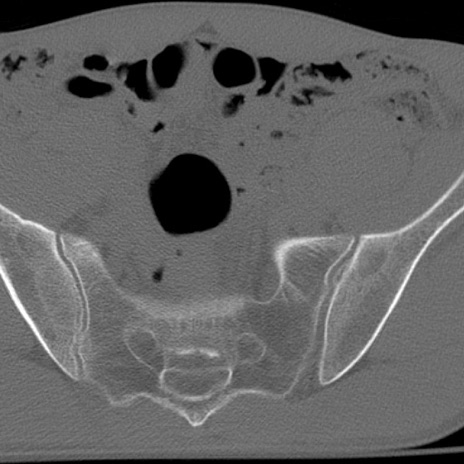

症例3 腰椎CT(横断像)

腰椎CT